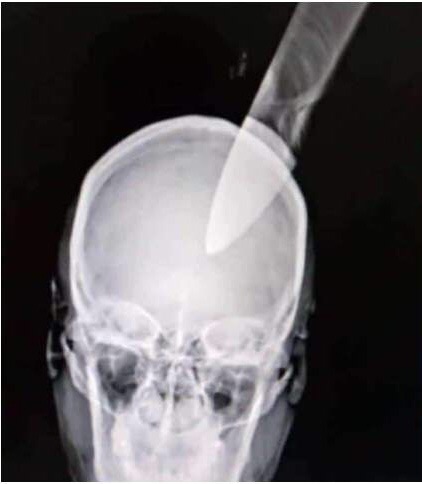

Adriana Martínez comenzó a pelear con su vecina. Sin embargo, en algún momento de la lucha terminó cayendo al suelo. En ese momento la otra mujer aprovechó para agarrar un cuchillo de cocina y clavárselo en la frente, reseñó El Siglo.

El objeto corto punzante penetró varios centímetros en la cabeza de la víctima, por lo que la llevaron de emergencia al Hospital José María Benítez. No obstante, en dicho centro de salud no contaban con los medios adecuados para atenderla, así que la trasladaron al Hospital Central de Maracay.

Una vez que estuvo estable los galenos la sometieron a una intervención quirúrgica durante la tarde del martes y lograron sacar el cuchillo. Un vocero del hospital comentó que luego de la operación, la mujer está en observación, aunque indicó que se está recuperando satisfactoriamente de su herida.